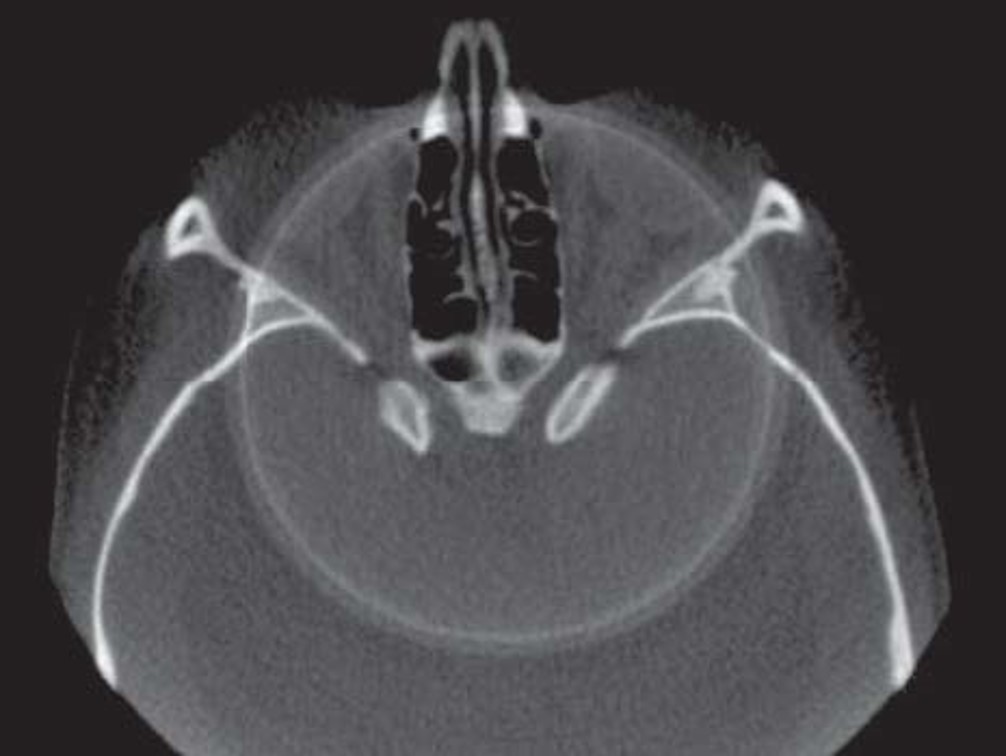

30) Identify the type of CBCT image. (1 mark)